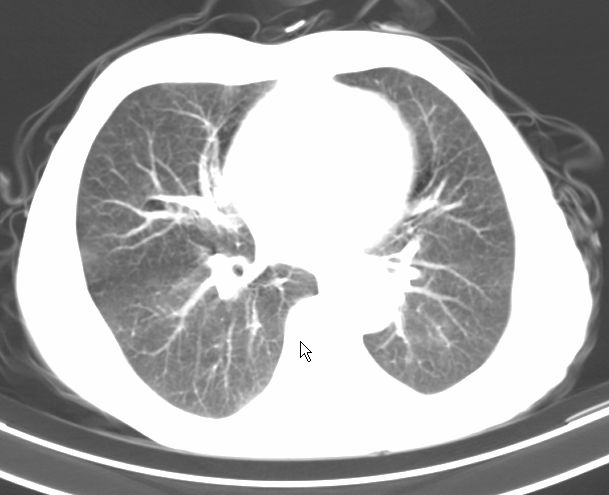

请大家看看是什么性质的。炎性病变首先考虑哪一种炎症。

支持右肺上叶前段\\下叶内基底段感染,建议抗炎治疗后复查,除外结核.

支持右肺上叶前段\\下叶上段感染,建议抗炎治疗后复查,除外结核.

支持右肺上叶前段、下叶内基底段感染,建议抗炎治疗后复查,除外结核.

右肺上叶前段及下叶内基底段感染性病变;建议抗炎治疗后复查。

楼主说是炎症,凭啥?典型的周围型肺癌(腺癌可能性大),肝内可能已有转移,强化看看吧。